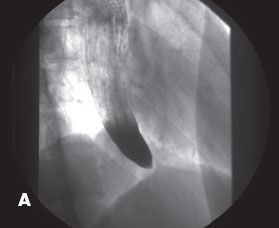

Esophagogastroduodenoscopy revealed a mildly dilated lower third of the esophagus (A). CT demonstrated a dilated esophagus (B). A barium swallow showed the classic “bird’s beak” appearance of the distal esophagus with proximal esophageal dilatation (C and D). A diagnosis of achalasia was made.